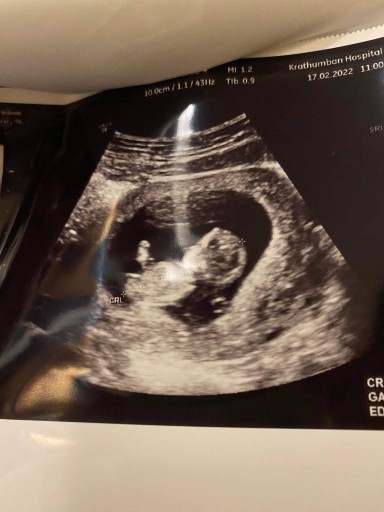

ต้าวเบบี๋ 12w4dค่ะ #ทีมสิงหา65🥰🥰🥰